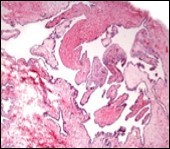

Typically, cutaneous ciliated cyst is a simple cyst which demonstrates a layering of pseudostratified ciliated columnar epithelium recapitulating conventional epithelial lining of the fallopian tube. As the cutaneous ciliated cyst demonstrates a morphological similarity to the fallopian tube lining epithelium, a Mullerian origin is indicated. Gross examination of cutaneous ciliated cyst depicts a solitary, mobile, non-tender, fluctuant, firm or soft to cystic lump with a fibrous wall and abundant amount of circumscribing adipose tissue. Cutaneous ciliated cysts are of a variable dimension. Cut surface usually displays a unilocular cyst impacted with clear, serous fluid, an attenuated smooth, greyish/ white cyst wall incorporated with incomplete septa traversing the cyst 6, 7.

Morphological analysis preponderantly demonstrates a solitary, uni-locular or multi-locular cyst of Mullerian origin with an epithelial lining recapitulating the epithelium of fallopian tube.

Cutaneous ciliated cyst is layered with a singular layer of ciliated epithelial cells which are chiefly constituted by cuboidal to columnar epithelium, traversed by partially configured fibrous tissue septa with an admixture of randomly dispersed, intraluminal papillary projections akin to those cogitated in the fallopian tube. Superimposed epithelium is inundated with well vascularized, parallel bundles of collagen although smooth muscle is absent 7, 8.

Figure 5.Cutaneous ciliated cyst with incomplete intervening septa and a lining of attenuated, ciliated epithelium along with supporting fibrous tissue (13).